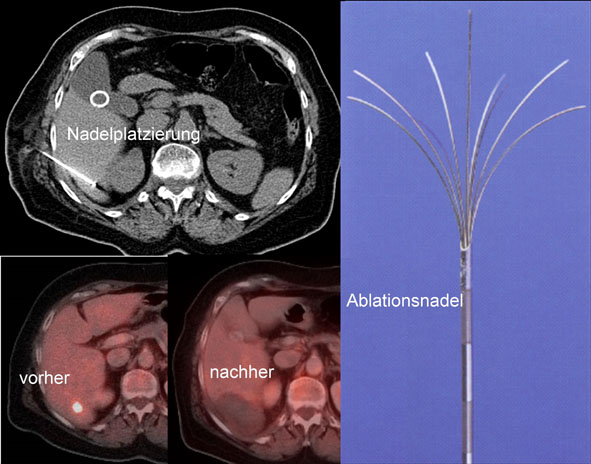

• Minimalinvasive Tumorablationen

• Biopsien (Sonographisch, CT, Angiographisch, Stereotaktisch, Multimodal 3D)